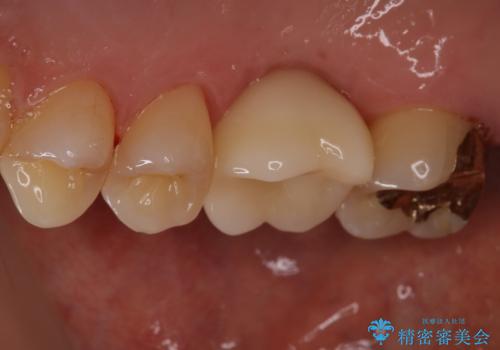

インプラント治療はブリッジと比較して、両隣の歯を削らなくてもよいというメリットがあります。

今回は両隣の歯を削りたくないとの希望がありましたので、インプラント治療を選択されました。